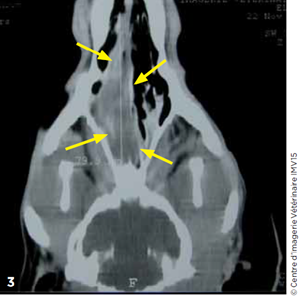

Un bilan d’extension local est réalisé à l’aide d’un examen tomodensitométrique des cavités nasales (Photos 23 et 4).

Un envahissement des cavités nasales droite et gauche par une masse à prise de contraste hétérogène est observé. Le bulbe olfactif et le lobe frontal droit sont envahis. Des images lytiques des

cornets nasaux, volutes éthmoïdales, septum, vomer, lame criblée et os frontal sont visualisées.

Photo 2 Examen tomodensitométrique. Noter l’envahissement bilatéral des cavités nasales (flèches).